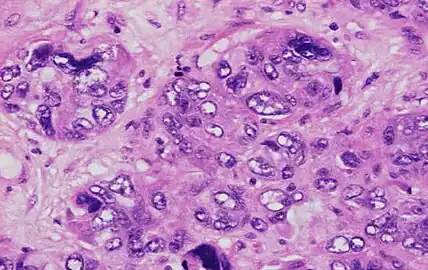

Nuclear pleomorphism

This parameter assesses whether the cell nuclei are uniform like those in normal breast duct epithelial cells, or whether they are larger, darker, or irregular (pleomorphic). In cancer, the mechanisms that control genes and chromosomes in the nucleus break down, and irregular nuclei and pleomorphic changes are signs of abnormal cell reproduction.

Note: The cancer areas having cells with the greatest cellular abnormalities should be evaluated.

- 3 points: nuclei with marked variation in size and shape

Invasive ductal carcinoma with marked nuclear pleomorphism.